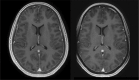

Materials and methods: Ten patients underwent routine brain MRI with 3 Tesla MR750w system and 12-channel head coil. T1-weighted gradient echo (BRAVO) and Silenz pulse sequence (TE=0, 3D radial center-out k-space filling and data sampling with relatively small gradient steps) were performed. Patients rated subjective sound impression for both sequences on a 6-point scale. Objective sound level measurements were performed with a dedicated device in gantry at different operation modes. Image quality was subjectively assessed in consensus by two radiologists on a 3-point scale.

Results: Readers rated image quality as fully diagnostic in all patients. Measured mean noise was reduced significantly with Silenz sequence (68.8 dB vs. 104.65 dB with BRAVO, P = 0.024) corresponding to 34.3% reduction in sound intensity and 99,97% reduction in sound pressure. No significant difference was observed between Silenz sound levels and ambient sounds (i.e., background noise in the scanner room, 68.8 dB vs. 68.73 dB, P = 0.5). The patients' subjective sound level score was lower for Silenz compared with conventional sequence (1.1 vs. 2.3, P = 0.003).